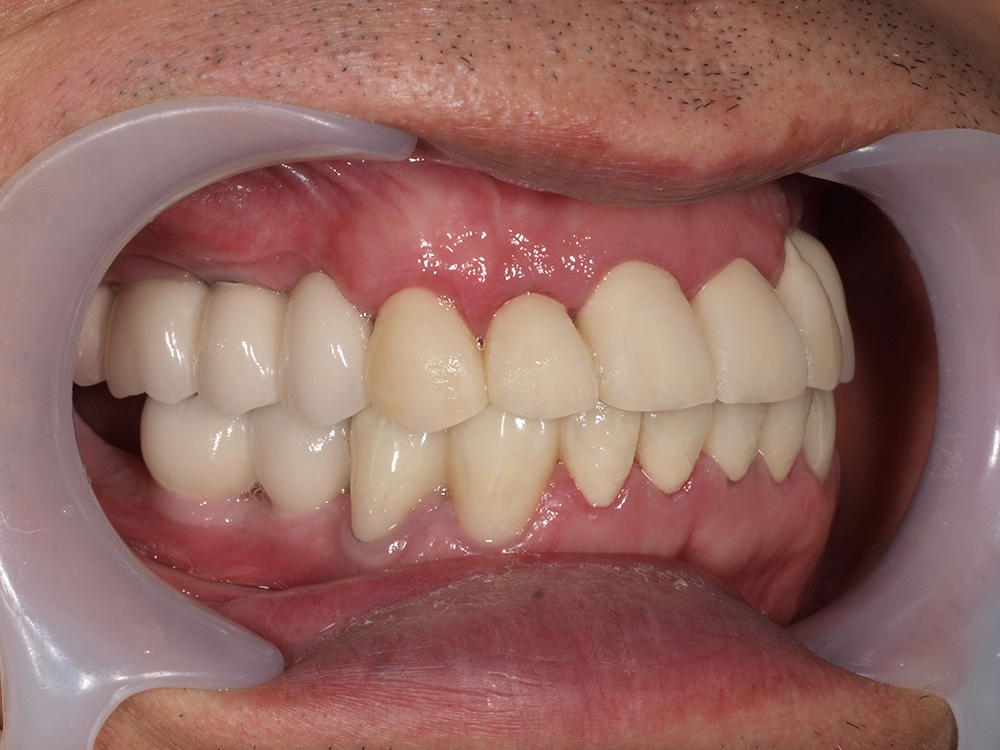

53歳 男性

- 主訴

- 全然噛めない。上の歯が取れてきた

- 処置内容

- 上顎:8本 下顎:2本

- 治療費用

- 上顎:約320万円(税込)、下顎:約160万円(税込)

- 治療期間

-

上顎:1年(仮歯まで8か月)

下顎:8か月(仮歯まで5か月)

- リスク

- 上部構造物、仮歯の破折、術後の腫れ(3日)、人工歯根脱落リスクがあります